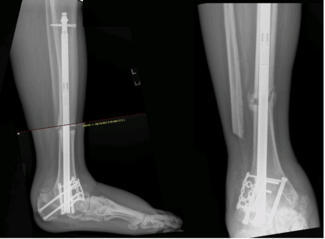

Focusing on surgical technique, these authors present an innovative approach to retrograde hindfoot nailing with compression-lengthening over nail (C-LON) with a review of 10 case studies.